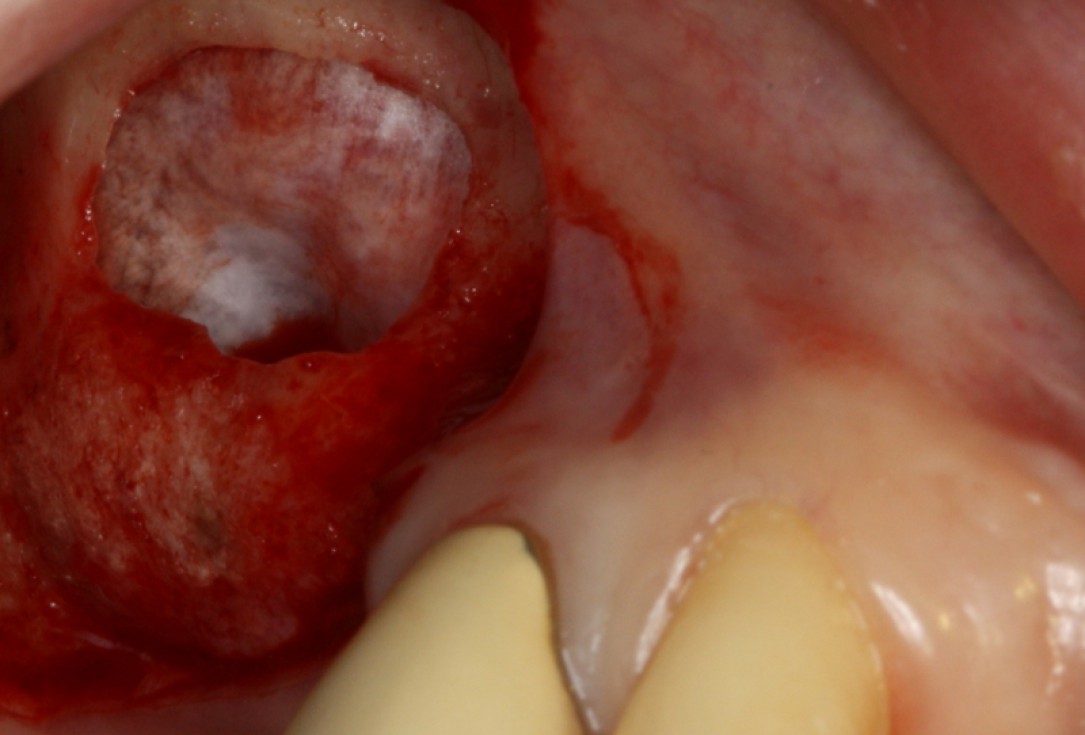

07/20 - Second surgical site: clinical situation preoperativelyGBR with maxresorb® & Jason® membrane - Prof. Dr. Dr. D. Rothamel

-